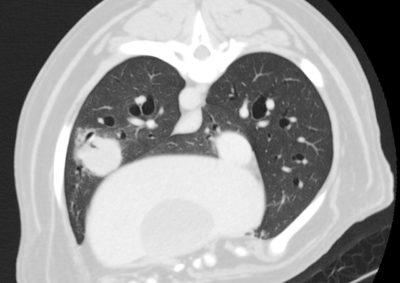

腫瘍外科 注意 ボタンをクリックした先に、治療中および手術中の画像が説明で使用されている場合がございます。 そのような画像に弱い方は閲覧なさらないようお願いいたします。 腫瘍外科 フレンチブルドッグ胃腺癌 胃部分切除 軟部組織外科腫瘍外科救急・集… 肝臓腫瘤破裂による腹腔内出血 腫瘍外科腫瘍内科 猫の直腸切除吻合 直腸リンパ腫 腫瘍外科 犬の肺腺癌の1例 腫瘍外科放射線治療 犬の軟部組織肉腫に対する腫瘍辺縁切除及び術後放射線療法 腫瘍外科 犬の肝細胞癌 軟部組織外科腫瘍外科 ジャックラッセルテリアの胃腫瘍 腫瘍外科 吻側下顎骨切除術〜メラノーマ〜 腫瘍外科 猫の上顎腫瘍切除 腫瘍外科 犬の脾臓腫瘤摘出 軟部組織外科腫瘍外科 大腸腺癌 軟部組織外科腫瘍外科 肺葉切除術 <1234567> 症例カテゴリー 放射線治療整形外科軟部組織外科脳神経外科内科腫瘍外科救急・集中治療リハビリテーション科腫瘍内科内視鏡科脳神経科呼吸器外科中医・漢方猫の腎移植循環器科